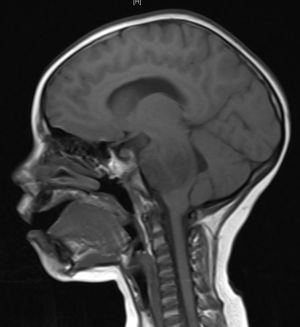

5. 1. 영상 검사

의학 영상은 뇌종양 진단에 핵심적인 역할을 한다. 초기에는 침습적이고 위험한 방법들이 사용되었지만, 현재는 비침습적이고 고해상도 기술인 자기 공명 영상(MRI)과 컴퓨터 단층 촬영(CT) 스캔이 주로 사용된다.[42]| 검사 종류 | 설명 | 특징 |

| 자기 공명 영상(MRI) | 뇌종양 진단에 가장 선호되는 영상 검사이다.[24][43] | 교모세포종은 T1 강조 MRI에서 조영 증강, T2 및 FLAIR 영상에서 고신호 뇌부종을 보인다.[24] 저등급 신경교종은 T1 MRI에서 저신호, T2 및 FLAIR MRI에서는 고신호를 보인다. 수막종은 MRI에서 경막 비후와 함께 균일하게 조영 증강된다.[24] |